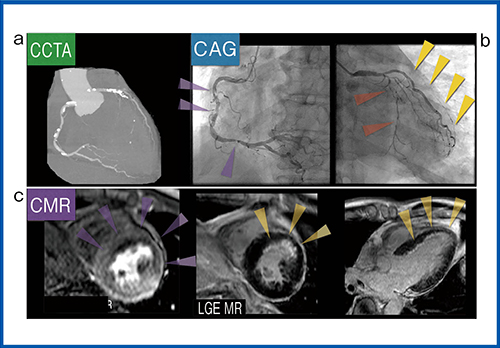

症例2(図4)は、60歳代、男性で、労作時胸痛の症例である。冠動脈CTでは、多数の石灰化と複数の狭窄病変が認められた。特に左前下行枝(LAD)の末梢の描出が悪く、カテーテルによる冠動脈造影検査を行った。カテーテル検査では、右冠動脈(RCA)および左回旋枝(LCX)に多数の中等度狭窄が認められ、LADは近位部からのCTO(完全閉塞)で前壁領域の強い虚血が疑われた。perfusion MRと遅延造影では、前壁から中隔にかけた広範囲な虚血と、前壁中隔に限局した内膜下梗塞が描出され、バイパス手術が行われた。

症例2のperfusion CTでは、MRIと同様に前壁から中隔の広範囲に虚血が描出された。線量を下げた撮影によるローテーションノイズやストリークアーチファクトなどによる偽陽性を防ぐため、PhyZiodynamicsで補完することで、ノイズを抑えたスムーズなperfusion画像が得られる。

図4 症例2:60歳代,男性,労作時胸痛

a:CCTA,b:CAG,c:心臓MRI(perfusion MR,LGE)

さらに、PhyZiodynamicsによる画像補完は、3DによるCT perfusionとCoronary CTAによる虚血の範囲と責任血管の評価に効果を発揮する。冠動脈とperfusion画像をフュージョンさせることで灌流域の評価が可能になるが、通常の1心拍30フェーズのデータでは1フェーズごとのCT値の変化が大きく、CT値による濃度変化の評価は難しい。PhyZiodynamicsで補完した3D画像では、動態補完によってCT値の濃度変化を観察するフレーム数が増えることで、心筋が染まる様子が滑らかに描出され、冠動脈との位置関係の評価がより明瞭になる。PhyZiodynamicsでは、画質の向上によって心筋全体のperfusion画像から、心外膜側に限らず図5のように心内膜側の血流情報の抽出が可能で、心内膜側と心外膜側の血流情報を分けて表示し、Coronary CTAによる冠動脈の血管の情報を組み合わせることで、位置関係を確認しながら虚血評価可能な画像を提供できる。

図6は、症例2の術前・術後の虚血領域を比較した画像だが、バイパス手術によってLAD領域の心外膜側では血流が回復しているが、心内膜側は術前に比べて変化が少ないことがわかる。バイパス術によって心外膜側の虚血は改善したが、心内膜側の内膜下梗塞は残存したことが評価可能であり、Dynamic Perfusion解析によって術後のフォローアップに有用な情報を提供することができる。